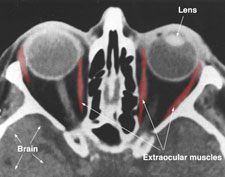

The eye has a visual acuity threshold below which an object will go undetected. This threshold varies from person to person, but as an example, the case of a person with normal 20/20 vision can be considered. As light enters the eye through the pupil, it passes through the lens and is projected on the retina at the back of the eye. Muscles called extraocular muscles, move the eyeball in the orbits and allow the image to be focused on the central retinal or fovea.